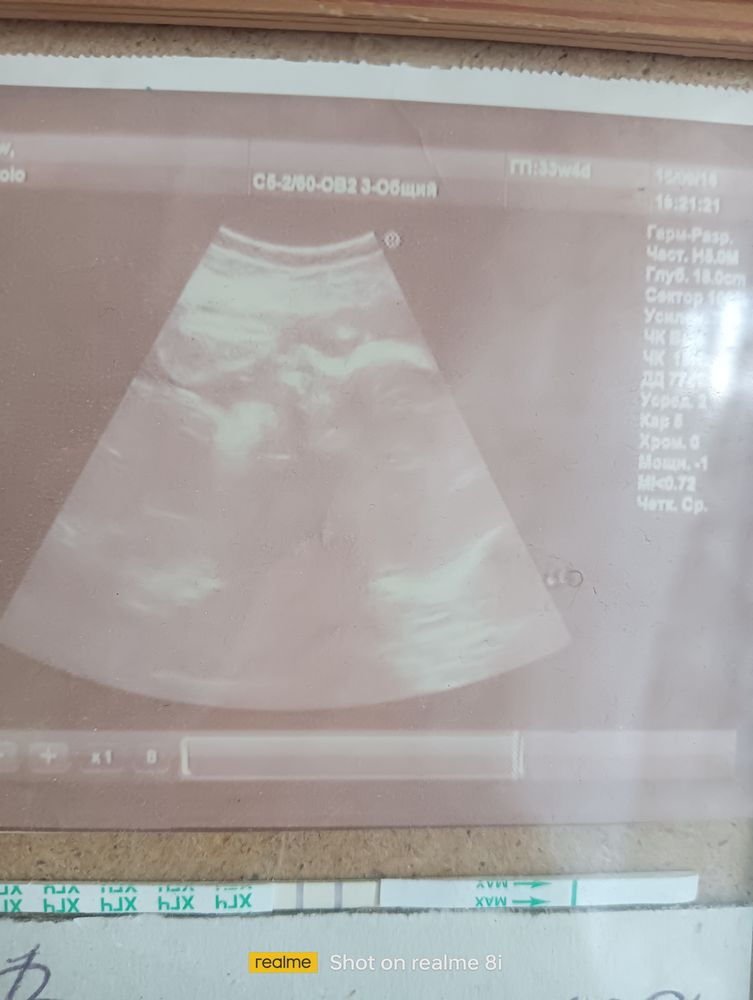

Помогите рассмотреть🙏 Мамочки!!!